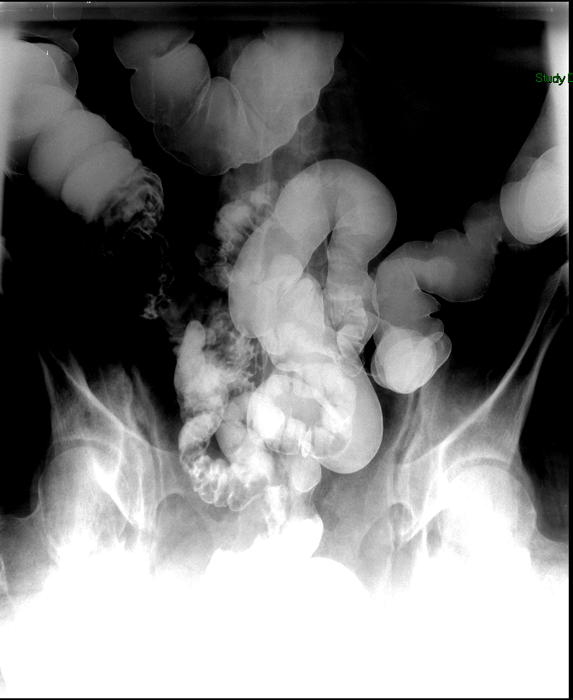

- Once 15 minutes has passed since the patient drank the barium, the technologist will obtain a prone (if possible) radiograph

(key image 2).

- Prone positioning is preferred because while lying prone, the weight of the body provides compression of the bowel loops.

- The film should include the entire stomach as well as the bowel that is filled with contrast.

- The technologist will obtain radiographs at 30, 45, and 60 minutes after the initial administration of barium. If the column of contrast material has not reached the large bowel on the 60 minute film, the technologist will obtain images every 30 minutes until contrast can been seen in the cecum

(key image 3)

(key image 4)

(key image 5).